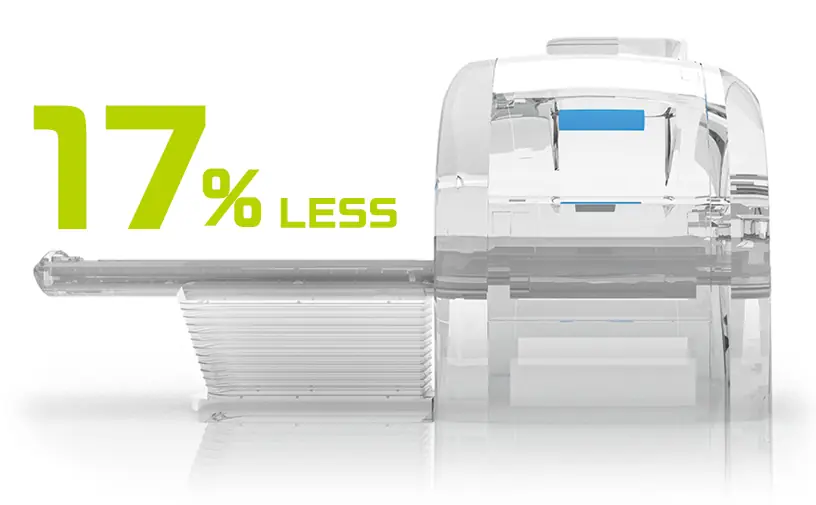

Gereksiz güç tüketimini en aza indirme

Genel olarak, süper iletken MRG sistemi yüksek işletme maliyetiyle bilinir. Bu maliyet esas olarak süper iletkenliği korumak için gerekli olan soğutma sisteminin yüksek güç tüketiminden kaynaklanır. ECHELON Smart Plus, kullanılmadığı dönemlerde soğutma sistemini belirli bir süre durdurabilen bir enerji tasarrufu işlevi olan SmartECO ile donatılmıştır. Bu işlev, helyum kaybına sebep olmadan güç tüketimini etkili bir şekilde azaltır. Dahası, bu süreler boyunca soğutma sisteminden gelen ısı emisyonu azaldıkça, ısı dağıtma ünitesinin güç tüketimi de azalır.

Daha az ısı tahliyesi olan bir MRG ünitesine sahip kompakt bir tarama odası, muayene ve ekipman odalarının iklimlendirme gereksinimlerini de azaltır. Isı tahliyesinin azaltılmasıyla birlikte enerji tasarrufu işlevi çalıştırma maliyetlerini %17*3 oranında azaltabilir

*3 Çalışma koşullarına ve diğer faktörlere bağlıdır.

*3 Çalışma koşullarına ve diğer faktörlere bağlıdır.